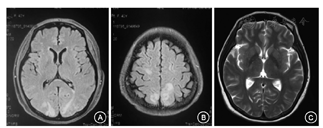

入院后完善检查:血常规:Hb 53 g/L,MCV 85.6 fl,RET绝对值19.8×109/L,WBC及PLT正常,Alb 29 g/L,LD 239 U/L,IgG 5.10 g/L,IgA 1.84 g/L,IgM 16.47 g/L,C4 0.040 g/L,C3 1.349 g/L。24hUP 2.69 g/24h,SPEP:M蛋白10.60 g/L。HBV-DNA 0.052U/L。冷球蛋白定性及定量:Ⅱ型(单克隆成分为IgMκ)、4.0%、1 112.5 mg/L;冷球蛋白检测HbsAg 0.050U/L。RF 11.4U/L,B型钠尿肽(BNP)369 ng/L。N末端B型钠尿肽原(NT-proBNP)7 424 ng/L,胸腹盆CT平扫:肝脾增大;腹膜后、盆腔及双侧腹股沟多发肿大淋巴结(大致同前);腹盆腔积液;胸腹部皮下组织水肿。骨髓涂片大致同前。考虑诊断Ⅱ型冷球蛋白血管炎(HBV相关),急性肾损伤,心脏受累不除外。于2018年9月7日、9月30日、10月20日、11月23日、12月24日、2019年1月22日、2月20日行第1~7程R-CP方案治疗,具体为:美罗华600 mg d0、环磷酰胺1.15 g d1、泼尼松100 mg d1~5。考虑患者为慢性HBV感染,且在抗病毒治疗中出现冷球蛋白血管炎加重,我们也对患者HBV耐药位点进行筛查,并未发现耐药,故将原有抗病毒治疗方案调整为恩替卡韦1 mg/次、1次/d。患者2程治疗后诉胸闷缓解、双下肢水肿消退及皮损好转,贫血及肾功能恢复至正常,复查NT-proBNP 564 ng/L,肾功能恢复后完善心肌MRI示:左房、左心室略增大;心包积液;室间隔基底段中层线样延迟强化,心肌病变不除外(图1)。治疗期间于2018年10月6日(第2疗程治疗第7日)曾出现剧烈头痛,外院头核磁共振弥散加权成像(MRI+DWI)示:双侧顶枕叶异常信号影(图2A、图2B)。行腰椎穿刺术,脑脊液常规、生化、白细胞介素(IL)-6、8、10均未见明显异常,脑脊液细胞未发现MYD88突变,脑脊液细胞学及免疫分型未见明显异常。此后无头痛再发。2018年11月14日行头部磁共振血管成像(MRA)及磁共振静脉成像(MRV)未见明显异常(图2C)。考虑为可逆性后部脑病综合征(PRES)。6程后复查血清蛋白电泳:M蛋白5.40 g/L,冷球蛋白定量:<1.0%、77.3 mg/L,C4 0.066 g/L,RF 4.883 U/L。HBV-DNA<0.02 U/L。

注:A和B为2018年10月6日外院头MRI检查图像;C为2018年11月14日复查头MRI T2W图像

患者治疗过程中出现头痛等中枢神经系统症状及MRI异常,冷球蛋白血管炎、小B细胞淋巴瘤均可有CNS受累,而患者脑脊液检查及查头MRV、MRA均正常。最终结合临床表现以及各项辅助检查结果考虑为PRES。

患者病程第二阶段是在治疗过程中出现了头痛及MRI异常,猜想可能的病因包括冷球蛋白血管炎累及中枢、小B细胞淋巴瘤中枢侵犯等。冷球蛋白血管炎累及中枢可表现为卒中、癫痫或认知障碍,通常的MRI表现为脑室旁、放射冠及半卵圆中心长TR序列对称性白质高信号[14,15]。而小B细胞淋巴瘤累及中枢神经系统最常见的为华氏巨球蛋白血症(Bing-Neel综合征)。但疑点在于头痛发作为治疗过程中,患者其他症状及实验室检查结果均好转,且此后患者再无头痛表现。因此我们对患者完善脑脊液检查,包括脑脊液免疫分型、脑脊液MYD88检测以及头MRA、MRV均未见明显异常。分析患者头痛发作时MRI主要表现为两侧对称的,顶枕叶为著的病变,且头痛及影像学改变为一过性,综合以上,考虑为PRES。PRES通常起病急,可由肾衰、血压波动、细胞毒药物的使用或子痫等情况诱发,表现为头痛、视野缺损、意识障碍或癫痫等[16,17]。结合本患者在治疗过程中发病及既往高血压病史,因此我们认为其可能的诱因包括化疗药物的使用或高血压控制不佳。